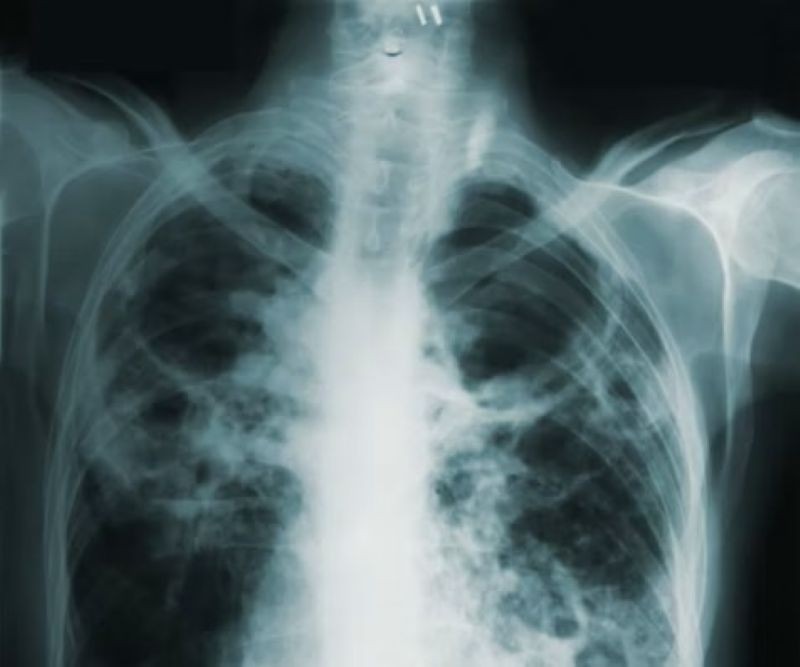

Tuberculosis

Shocking WHO report: TB killed 1.2 million people in 2024

Tuberculosis (TB) remains one of the world’s deadliest infectious killers, claiming over 1.2 million lives and affecting an estimated 10.7 million people last year, according to the WHO Global Tuberculosis Report 2025, released recently.